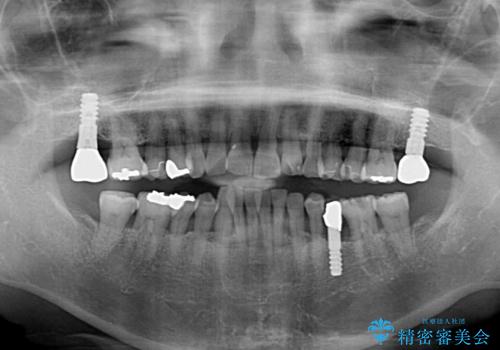

- 近医にてインプラント治療を行った後に矯正治療を希望され、来院された患者様です。

口元の突出感とデコボコが気になっているとのことでしたが、インプラントが既に3本埋入されていたため、抜歯矯正による口元を引っ込めることができない状況でした。

近医での歯周病治療の影響でブラックトライアングルが発現していたため、IPR(歯と歯の間を削る)で隙間を改善しつつ、インプラントを固定源に歯列全体を後方へ移動させることとしました。

インプラントは矯正治療では動かすことができないため、インプラント治療を行う前に矯正治療を行う意思があるのかを確認します。

特に出っ歯などで抜歯矯正となる場合には、インプラントが邪魔になることがあるので注意する必要があります。